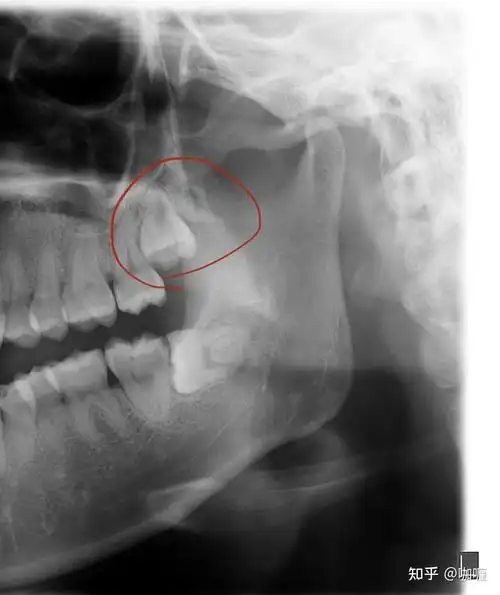

智齿是由于人类颌骨缺乏足够的空间来容纳所有的牙齿,导致最后萌出的

原来"拔智齿"也是有最佳年龄的?医生提醒:这6类人谨慎拔智齿_患者_进